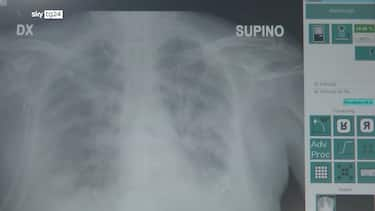

La polmonite, prosegue il presidente di Aipo, è un’infezione che “può essere localizzata in un punto particolare del polmone. L’ente patogeno più frequente in questo caso è lo pneumococco, contro il quale esiste appunto una vaccinazione. Esistono poi le polmoniti interstiziali che colpiscono il tessuto connettivo del polmone, l’area dove avviene lo scambio, per questo l’infezione può essere molto diffusa e anche bilaterale. E’ dovuta prevalentemente a virus, il Covid tra questi, come abbiamo visto durante la pandemia, e ad alcuni batteri. Altro caso abbastanza emblematico è la legionella, oppure i cosiddetti agenti intracellulari, micoplasma e clamidia”. Ma quali sono i segnali d’allarme che indicano una possibile polmonite? “Una polmonite si presenta prevalentemente tosse e febbre”, descrive lo pneumologo. Ma la “gravità che causa ospedalizzazione riguarda la difficoltà respiratoria, che può essere altamente rischiosa”, conclude.

Per distinguere una polmonite dai tipi diversi di microorganismo bisogna fare un tampone. I sintomi si possono gestire col cortisone, che è una terapia anti-infiammatoria molto potente, o con altri farmaci antinfiammatori in uso, afferma Bassetti in un’intervista al Messaggero.  Il primo sintomo della polmonite, ribadisce l’esperto, riguarda l’insufficienza respiratoria, cioè fondamentalmente si ha la dispnea, cioè la difficoltà a respirare. Con la desaturazione, cioè il saturimetro ci dice che la saturazione che normalmente è intorno al 95% scende a 90, 89, 88, 87, quindi c’è una difficoltà a scambiare l’ossigeno a livello polmonare. Poi ci può essere la febbre e la tosse, che in genere se c’è una forma interstiziale è secca, se invece c’è una forma più facilmente batterica, una tosse grassa, magari una tosse con anche un espettorato rugginoso (ovvero colorito tendente a appunto al marroncino, al rossastro), può esserci un dolore abbastanza tipico a livello del del petto, a livello della schiena, che in genere è tipico della polmonite. A tutto questo si aggiunge stanchezza, spossatezza.

“Se si hanno dei sintomi compatibili con la polmonite bisogna farsi vedere da un medico, quindi evitare di curarsi da soli” dichiara Bassetti al Messaggero.  Fare una visita dal medico, una radiografia del torace o una TAC per vedere che non ci siano, appunto, dei segni di polmonite e poi, naturalmente, fare un’adeguata diagnostica, cioè fare il tampone per vedere se è un virus, per vedere se è un batterio e a quel punto poi di gestire come come curarlo. Le polmoniti batteriche hanno bisogno di una terapia antibiotica per almeno 7 giorni e si guarisce completamente. Per le polmoniti virali si può usare la terapia antivirale, quella, per esempio, da influenza con l’oseltamivir e quella da Covid con il remdesivir che sono le due farmaci antivirali, mentre per tutti gli altri tipi di virus, purtroppo grossi farmaci non ce ne sono, quindi bisogna cercare di gestire al meglio i sintomi.